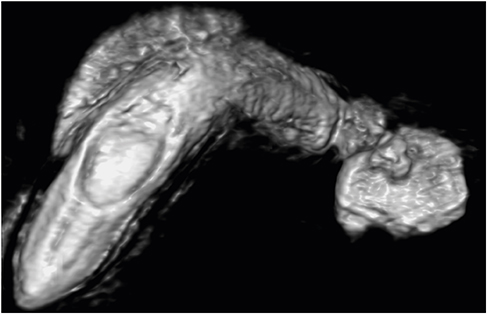

After admission, a follow-up MRCP (Fig. 1) and ultrasonography (Fig. 2) revealed a 1.7 cm-sized cystic lesion around the CBD and duodenum showing no definite communication with the CBD, indicative of a duodenal duplication cyst causing biliary obstruction or an unusual choledochal cyst or choledochocele. To evaluate the relationship between the cystic lesion and the duodenum, a upper gastrointestinal series and computed tomography were taken and showed mild narrowing at the proximal duodenum with no evidence of communication between the cyst and the duodenum. However, the structural continuity between the cyst and the biliary tree still remained unclear, so a percutaneous transhepatic cholangiography (Fig. 3) was performed and revealed a cystic lesion located at the confluence level between the common hepatic duct (CHD) and cystic duct (CD) with possible communication with the CD, highly suggestive of Todani type II choledochal cyst.

Fig. 3

Percutaneous transhepatic cholangiography showing 1.7 cm-sized cystic lesion.